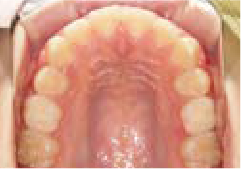

さらに、上からあごの骨を見たところ、中央がくびれた“ひょうたん型”に変形しており、あごの成長にも偏りが見られました。

診断の結果、前歯の中心も少し左にずれており、特に犬歯が生えるスペースが足りない状態でした。